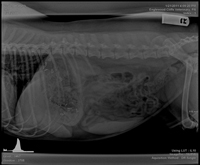

Grand Prize Winner

Vanessa Hawksin, DVM

Bayshore Animal Hospital

Warrenton, Ore.

Handball

The dog was presented for lameness in a hind leg, and while taking radiographs looking for musculoskeletal abnormalities, nine handballs were discovered as an incidental finding.